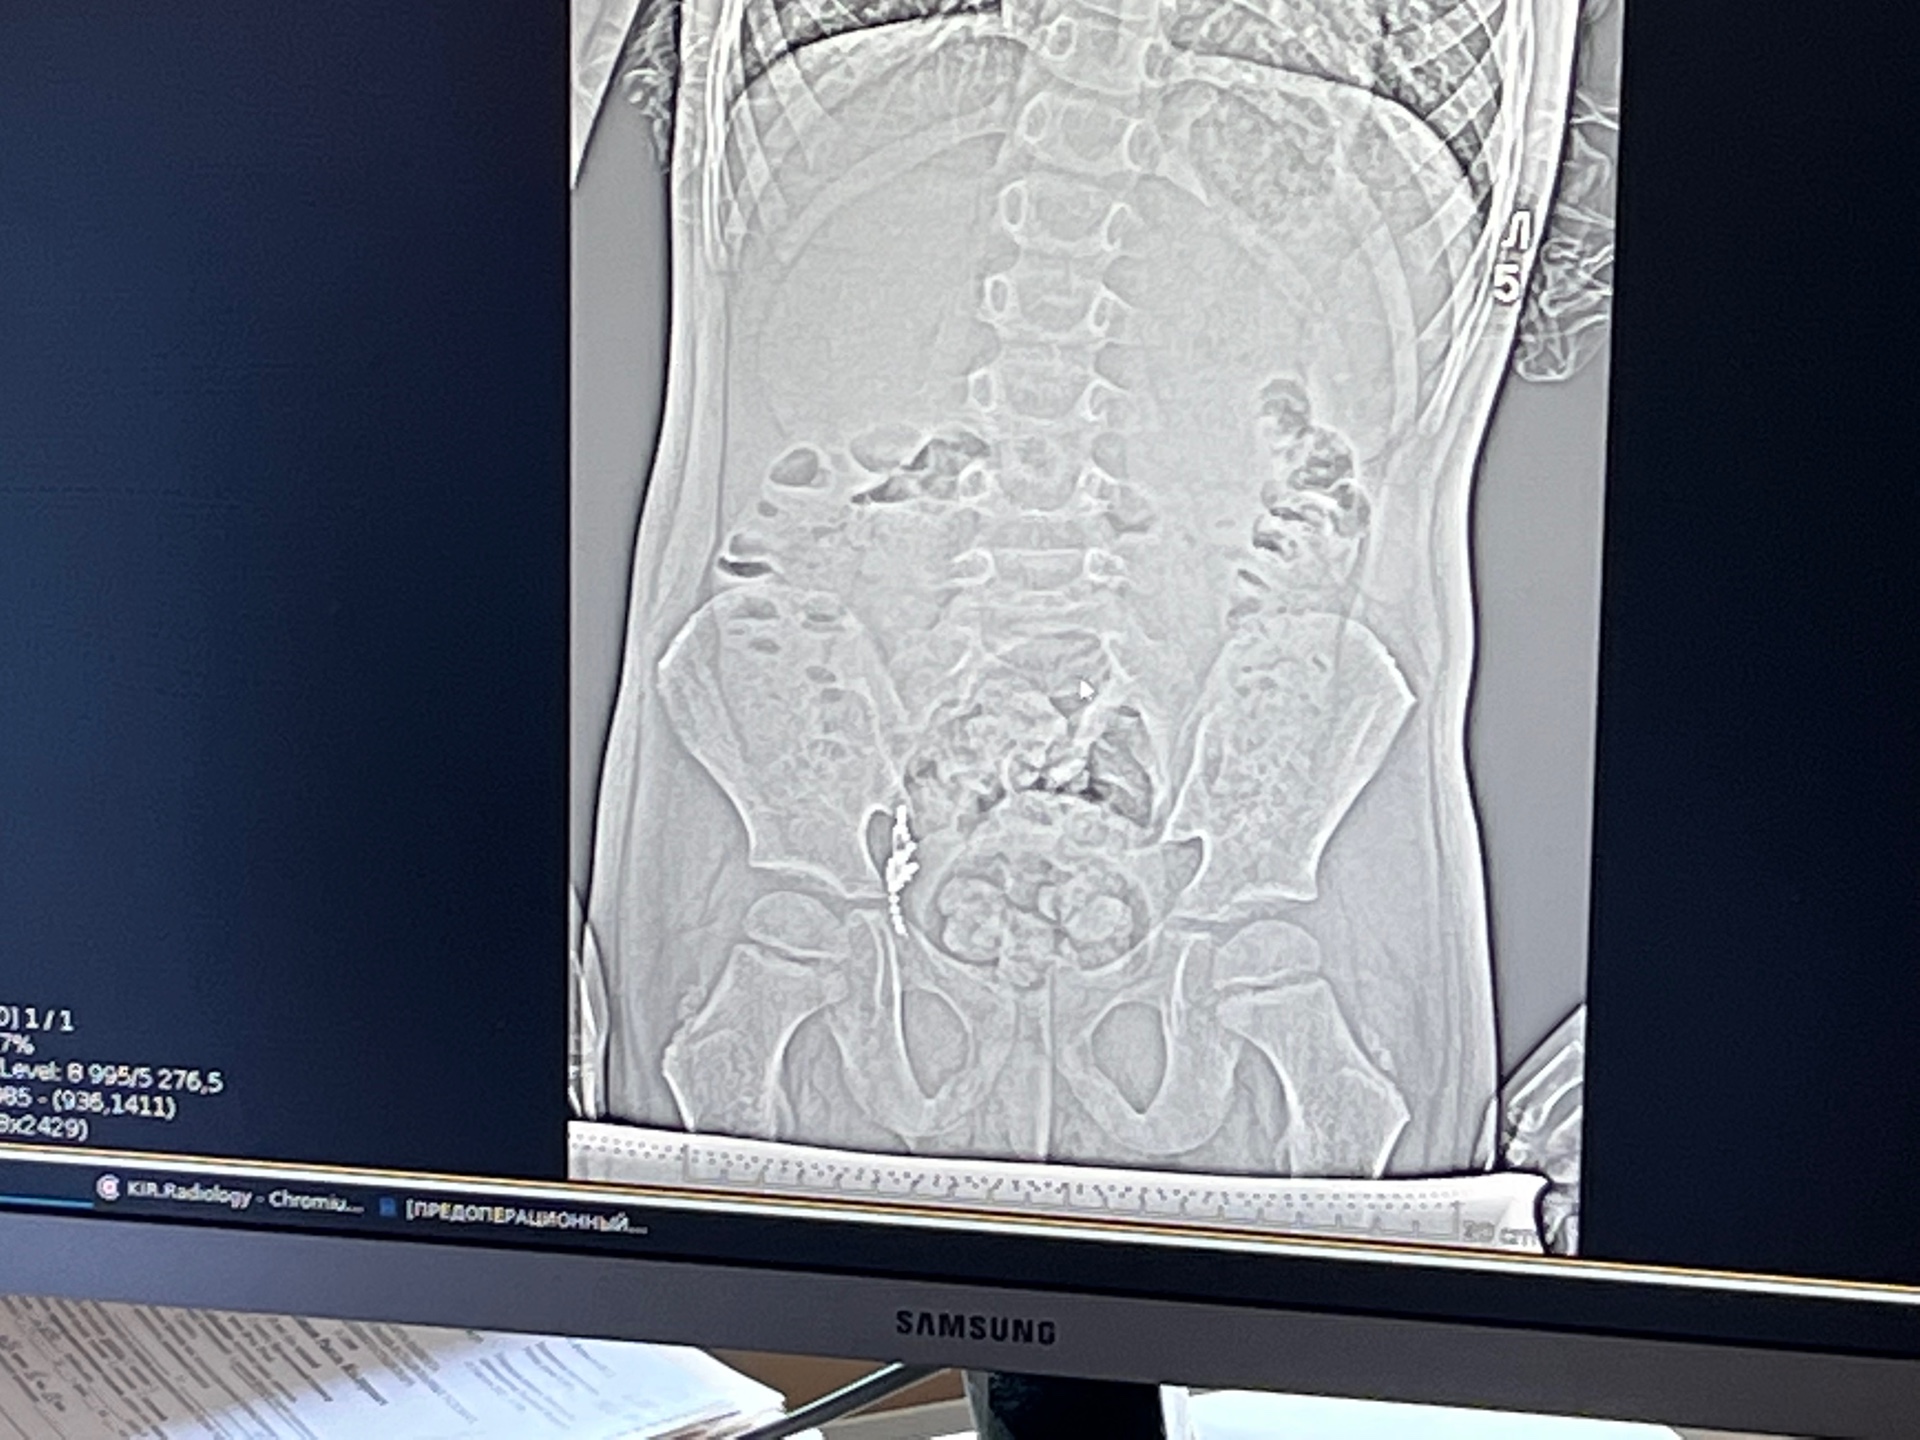

Для оказания помощи пациента направили в Камский детский медицинский центр г. Набережные Челны. Проведя компьютерную томографию, рентгенологи определили локализацию инородного тела. Выяснилось, что цепь попала в просвет червеобразного отростка (аппендикса), что встречается крайне редко.

Хирургам пришлось удалить аппендикс вместе с опасной находкой из-за невозможности извлечь ее другим способом.